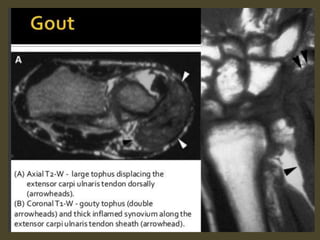

Tenosynovitis of Extensor Carpi Ulnaris.

Extensor carpi ulnaris tenosynovitis. Axial FS T2-WI shows fragmentation into multiple tendon fragments of